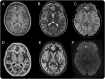

Methods: Retrospective review of clinical records, EEG, MRI, and histopathology in 32 patients with drug-resistant epilepsy and MRI-positive (72% 3.0 tesla), pathologically proven (type 2B cortical dysplasia) BOSDs operated at our centers during 2005-2013.

Results: Localization of BOSDs was frontal in 19, insula in 5, parietal in 5, and temporal in 3, on the convexity or interhemispheric surfaces. BOSDs were missed on initial MRI at our centers in 22% of patients. Patients presented with focal seizures during infancy in 9, preschool years in 15, and school years in 8 (median age 5 years). Seizures were stereotyped, predominantly nocturnal, and typically nonconvulsive, with semiology referable to the fronto-central or perisylvian regions. Seizures occurred at high frequency during active periods, but often went into prolonged remission with carbamazepine or phenytoin. Intellect was normal or borderline, except in patients with seizure onset during infancy. Scalp EEG frequently revealed localized interictal epileptiform discharges and ictal rhythms. Patients underwent lesionectomy (median age 14 years) guided by electrocorticography and MRI, with prior intracranial EEG monitoring in only one patient. Twenty-eight patients (88%) became seizure-free, and 20 discontinued antiepileptic medication (median follow-up 4.1 years).

Conclusions: In patients with cryptogenic focal epilepsy, this clinical presentation and course should prompt review of or repeat MRI, looking for a BOSD in the frontal, parietal, or insula cortex. If a BOSD is identified, the patient might be considered for single-stage lesionectomy.